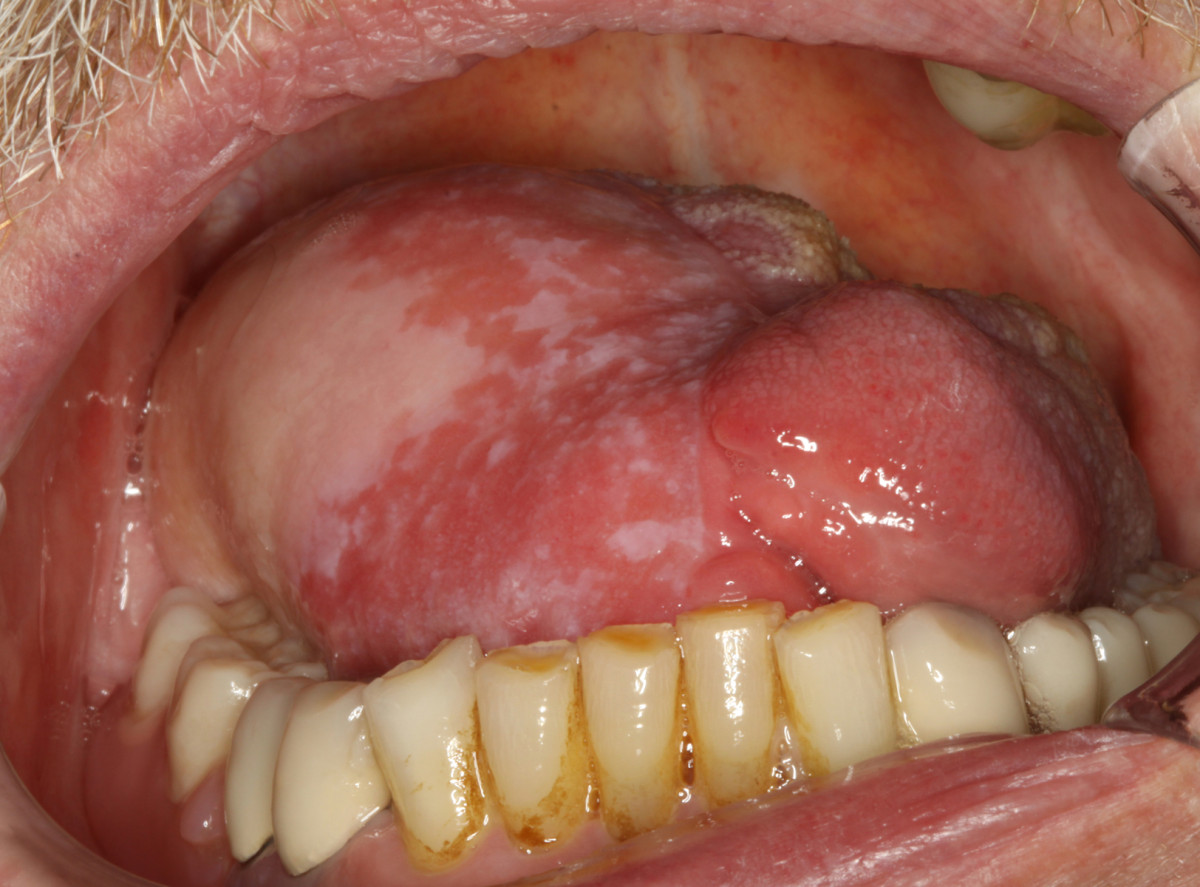

The overall survival rate of our patients with tongue cancer still lies within the range of survival rates decriped by other authors, which are quoted between 40 and 65%(7)(8)(9)(11)(24). We have to keep in mind that our study reviews a period of three decades and that treatment strategies have changed during this period towards a more aggressive course(43)(44). On the base of our results with high locoregional recurrence rates even in early stages of tongue cancer, we generally recommend extended resections on the primary site and categorical bilateral lymphadenectomy of at least level I-III in order to reliably remove occult lymph node metastases which can not be detected even by modern imaging techniques. In case of an open staging procedure with histologically approved lymph node metastases during surgery, a comprehensive neck dissection should complete lymphadenectomy(45). As described before, neck dissection procedures are only associated with a low morbidity(46). Modern reconstructive techniques with microvascular tissue transfer [Figure 12] help to keep functional impairment after partial glossectectomy tolerable and at least allow to refill substancial loss of soft tissue after total glossectomy(47) [Figure 13]. According to our results, radical surgery also provides considerable survival rates for advanced stages of tongue cancer and should be recommended as treatment of first choice. Adjuvant treatment modalities should be applied more frequently in controlled clinical trials and should generally be implemented in cases with unclear margins and lymphatic spread.

Figure 13 Thumb

Figure 13. Reconstructed defect of the toung. Final result of the anterolateral thigh flap (ALT flap) after 6 month.

Click image to view larger.